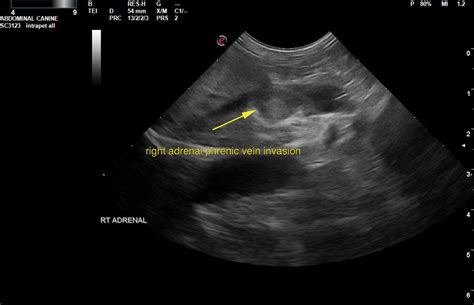

Imaging Studies

To determine the physical characteristics of the mass, the following imaging studies may be used:

- CT Scan (Computed Tomography): Often the first-line imaging modality to assess the size and appearance of the mass.

- MRI (Magnetic Resonance Imaging): Provides detailed information about the tissue composition to help distinguish between benign and malignant tumors.

- Surgical Removal (Adrenalectomy): If the tumor is large, appears suspicious for cancer, or is producing excess hormones, surgical removal is often the recommended course of action. This is frequently performed using minimally invasive techniques, such as laparoscopic surgery, which results in faster recovery times.